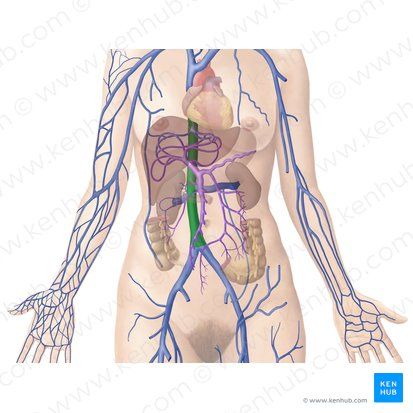

Hepatic Portal Vein

A large vein that carries deoxygenated but nutrient-rich blood from the digestive organs (stomach, intestines, spleen, pancreas) to the liver for processing.

Inferior Vena Cava

A large vein that carries deoxygenated blood from the lower and middle body back to the heart.